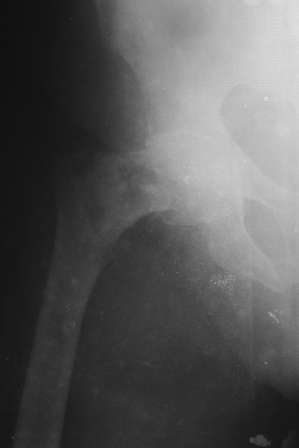

Доставлена   больная   72  года.  3  дня  назад  упала.  На   R-грамме

чрезвертельный  простой АО 31А1  перелом   левой  бедренной   кости.

Кроме  того  имеется  подозрение  на  субкапитальный  31В1  перелом ,  у

меня  на  практике  такое  впервые.  Трижды  сделали  R-графию,  но

качественный  снимок  не  получилось. КТ  в  диагностическом   центре

на  ремонте.

1.  Действительно ли  имеется субкапитальный   перелом,  или  мне

так  кажется?